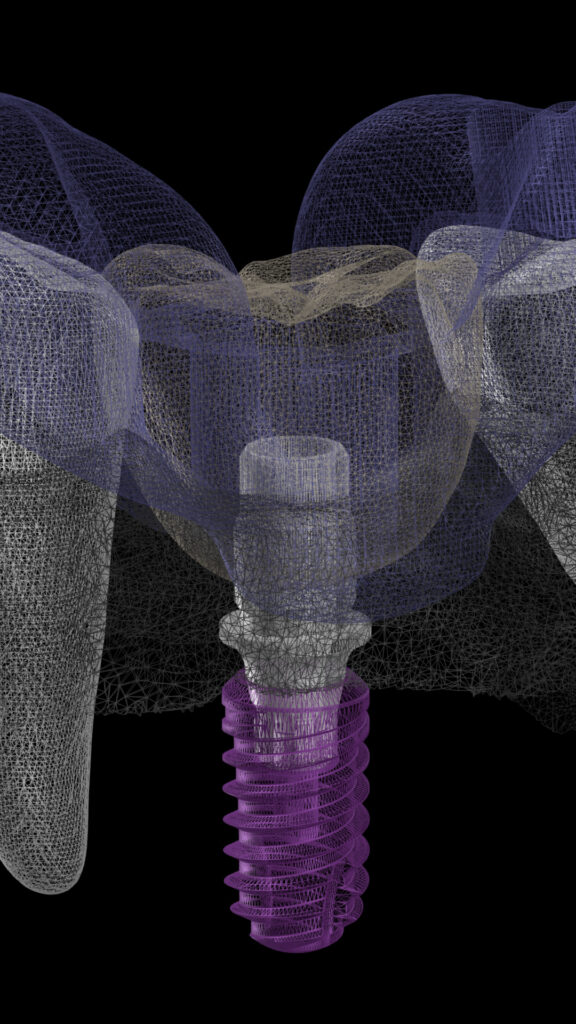

Mastering Implant Dentistry

Course Overview

Basic Pronciples, Biologic Principles, Ti-bases, Multiunit, Material Selection, Implant supported crowns and bridges, Full Μouth Rehabilitation, Occlusion)

CBCT Analysis, Preoperative placement planning based on CBCT, Implant and System Selection

Hands-on 2: Free-Hand Implant Placement

Hands-on 3: Guided Implant Placement